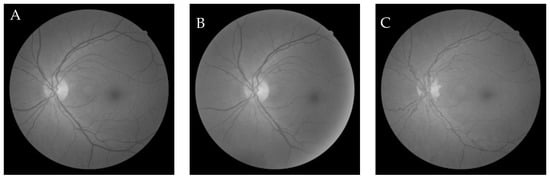

6.3. Comparative Study of the GWO-Based Different Demons Registration